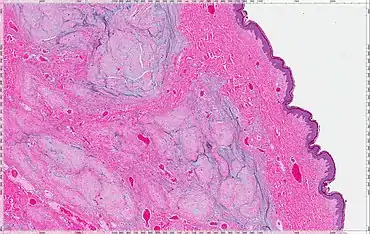

Micrograph of an atrial myxoma. H&E stain. | |

A myxoma (New Latin from Greek muxa 'mucus') is a myxoid tumor of primitive connective tissue.[1] It is most commonly found in the heart (and is the most common primary tumor of the heart in adults) but can also occur in other locations.